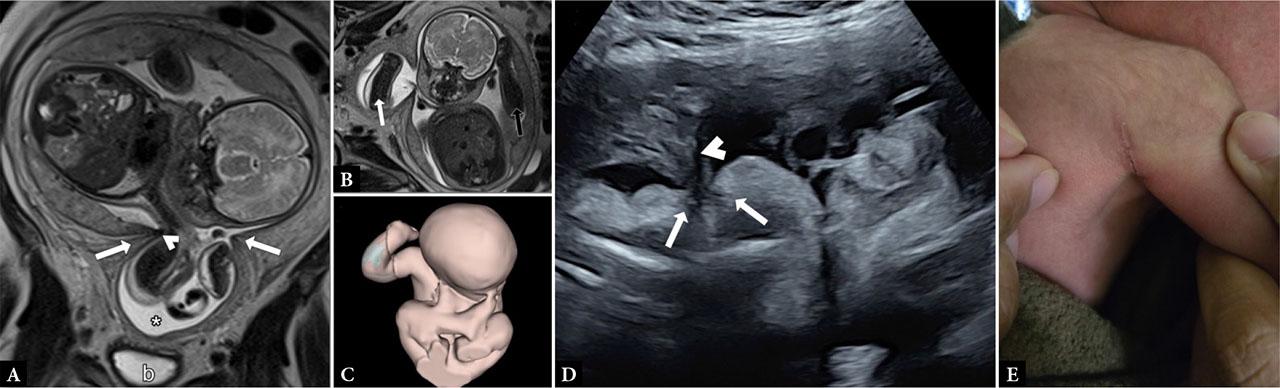

Fetus at 35 weeks of gestation. (A) T2-weighted magnetic resonance imaging (MRI) sequences demonstrate the uterus with a thick myometrial ring separating it into two segments (arrows). The right arm is entrapped in the lower uterine segment (asterisk), with part of the amnion in constant contact with the right axilla (b – bladder). (B) T2-weighted images demonstrate the difference between the left arm (black arrow) and the right arm (white arrow). The right arm shows a hyperintense signal in the subcutaneous tissue, corresponding to localized skin edema. (C) Three-dimensional reconstruction of MRI images of the fetus. The fetal forearm shows edema (blue) and is restricted to the lower uterine segment. (D) Ultrasound image showing the amniotic membrane (white arrows) originating from the uterine constriction ring (arrowhead), rupturing and infiltrating the fetal skin, with striated hypoechoic fibers. (E) Postnatal image of the neonate at the first week of life, showing the scar resulting from the lysis of the amniotic band

T2-weighted MRI sequences demonstrated the fetus in a transverse position. The uterine cavity showed a distinct narrow annular constriction in the inferior portion of the uterine body, suggestive of myometrial fibrosis. The fetus remained fixed in position throughout the acquisition of the sequences, with the right arm restricted to the lower uterine segment. Fetal anatomy was otherwise normal, although a hyperintense signal was observed in the subcutaneous tissue of the right arm, which appeared entrapped in the lower uterine cavity compared with the left arm. Absence of arm movement was also noted (Fig. 1. A–C and Video S1).

Because of the persistent absence of fetal movement in the right arm during MRI image acquisition, an ultrasound examination was performed using a Voluson E10 system (v. BT19; Madison, Wisconsin, USA). Doppler evaluation revealed normal blood flow in the arm, and the suspected subcutaneous edema was not confirmed. The fetus remained in a transverse presentation, and external maneuvers were performed to assess the integrity of the fetal skin and to exclude an amniotic band. Despite attempts to mobilize the fetus, its position remained unchanged. After intense external maneuvers, an amniotic band was visualized. The hyperechogenicity of the fetal skin was interrupted by the amniotic membrane, which showed hypoechogenic striated bands with shallow penetration into the fetal thorax. The continuity between the amniotic membrane and fetal skin, along with membrane infiltration into the skin, confirmed the diagnosis of ABS (Fig. 1D and Video S2).

The pregnancy progressed until 37 weeks, when the development of preeclampsia and a shoulder presentation necessitated delivery by cesarean section. Following delivery, the amniotic band was carefully separated from the skin over the posterior shoulder and axilla, leaving a small linear scar on the right side of the neonatal dorsum (Fig. 1E). The male neonate weighed 2,300 g, and both arms appeared normal on physical examination with preserved function. The newborn was admitted to the neonatal unit for five days due to jaundice but was discharged home without sequelae.